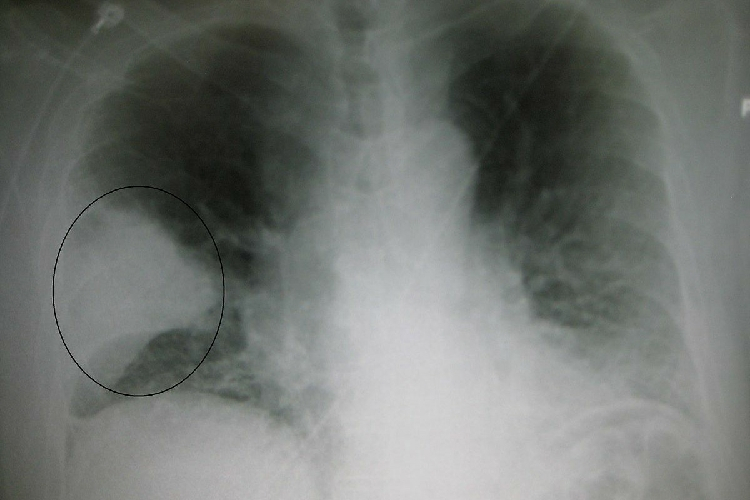

Девизом этого года является: „Каждое дыхание имеет значение!” Пневмония - это респираторное заболевание, которым очень часто болеют дети. Это одна из основных причин смерти среди детей в возрасте до 5 лет, убивающая 2400 детей в день во всем мире.

Пневмония вызывается инфекционными агентами, включая вирусы, бактерии и грибы, наиболее распространенными инфекционными агентами являются Streptococcus pneumoniae, Haemophilus influenzae типа b (Hib) и респираторно-синцитиальный вирус.